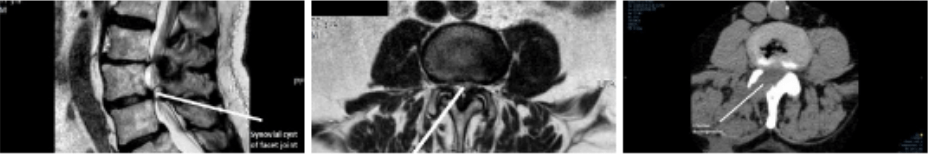

Figure 3 - Post-op CT

His symptoms were immediately relieved and he left hospital 48 hours after surgery. A postoperative CT scan (figure 3) showed the effective decompression, including of the central canal and the left side.